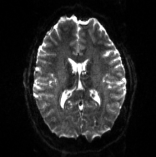

3.7 Comparison of PyHySCO with HySCO and TOPUP

Table 6 reports the runtime and correction quality for PyHySCO using GN-PCG, HySCO, and TOPUP. On real 3T and 7T data, PyHySCO achieves lower loss and higher relative improvement between corrected images than HySCO, and higher relative improvement than TOPUP. The runtime on CPU for real data is 1-2 minutes for HySCO and over 1 hour for TOPUP, while PyHySCO on GPU has runtimes of 10-13 seconds. For the simulated dataset, PyHySCO requires an average of 1 minute on GPU, HySCO an average of 12.6 minutes on CPU, and TOPUP an average of 8.5 hours on CPU. Using the ground truth field maps from the simulated dataset, PyHySCO achieves the lowest average field map relative error, 14.48%, compared to 19.70% for HySCO and 16.36% for TOPUP. Figures 7, 8, and 9 show the field map and corrected images for one example subject from each dataset. The results of the methods are similar, and the resulting field maps are comparable to those of the existing tools, HySCO and TOPUP, while PyHySCO is considerably faster.